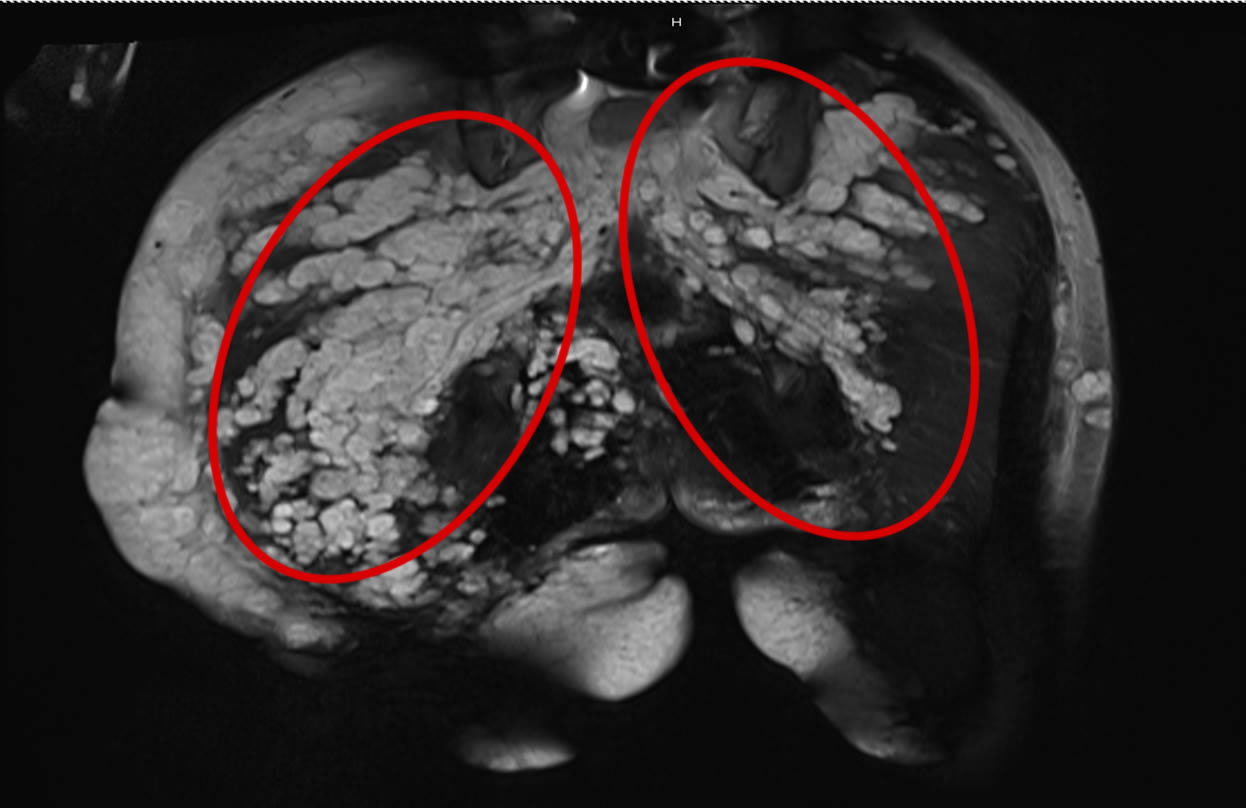

IRM du bassin démontrant un neurofibrome plexiforme

Les neurofibromes plexifomes ont également la possibilité de subir une transformation maligne (tumeur plus agressive) chez 20% des patients qui en présentent. Cette transformation se fait habituellement au cours de l’adolescence et de l’âge adulte. Les signes suggestifs d’une transformation maligne sont une croissance rapide de même que l’apparition d’une perte de fonction (par exemple de la faiblesse) et de douleur. Par contre, ces signes peuvent être constatés même en l’absence de malignité.

Des examens radiologiques (résonance magnétique (IRM), et en médecine nucléaire) permettent parfois de préciser la nature de ces lésions. En cas de doute, la lésion peut être biopsiée (une petite partie de la tumeur est retirée chirurgicalement) ou réséquée complètement, selon la localisation.